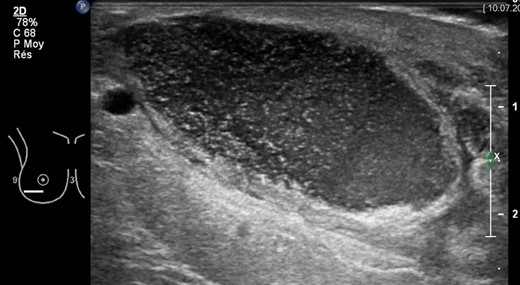

A 36-year-old Caucasian heavy smoker (1 pack/day), with no other comorbidities, presented with bilateral symptomatic breast hypertrophy. Reduction mammoplasty was performed following Thorek's technique [5]. Standard disinfection was performed with antiseptic povidone–iodine and 600 mg of intravenous (IV) clindamycin was delivered at anaesthesia induction. More than 1.1 kg of tissue was retrieved from each breast. Three weeks postoperatively, wound dehiscence associated with discharge was noted on the inferior border of the right breast. Neither redness nor heat was detected locally. The patient was apyrexial with no inflammatory syndrome (WBC count 11 g/l and C-reactive protein 6 mg/l). A smear of the discharge with liponecrosis showed low quantities of P. avidum. No antibiotic therapy was introduced at this moment and dressings with argentic sulfadiazine were prescribed every 48 h (Ialugen-plus, IBSA, Switzerland). Seven weeks postoperatively, a new red and tender induration in between the inferior quadrants of the right breast was noted. Interestingly, the patient remained apyrexial with no inflammatory syndrome. A breast ultrasound (US) showed a 4 × 4 × 15 cm encapsulated collection (Fig. 1). The abscess was drained and bacteriological examination of the purulent fluid revealed a larger quantity of P. avidum. Amoxicillin–clavulanic acid three times/day IV was started as empirical treatment for soft tissue infection. During the IV antibiotic treatment, no differences were seen in blood test parameters; however, a clinical improvement was evident with the discharge steadily decreasing. A control breast US on Day 5 post IV treatment showed remission of the abscess (Fig. 2). Results of antibiogram analysis confirmed the bacteria presence and its sensitiveness to amoxicillin–clavulanic acid. IV antibiotherapy was continued cessation of wound dehiscence (2 weeks), and then switched to oral amoxicillin for 1 month (750 mg three times a day). A breast US 1 month later showed abscess resolution and antibiotic therapy was discontinued. On physical examination, the infection had healed, and no surgical reintervention was needed (Fig. 3).

Complete wound healing after 6 weeks of antibiotic treatment and local dressings.